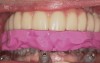

An important prosthetic consideration is knowledge of the appropriate implant position based on the type of restoration planned (cement- or screw-retained). Small variations in implant positions can lead to difficult restorative dilemmas. Accurate and predictable implant positioning using guided implant planning and placement can be critical to the esthetic and functional success of the restoration30 (Figure 8 through Figure 11).

Guided implant surgery involves reverse treatment planning. The ideal contour and arch position of the restoration is planned first, followed by virtual planning of the implant into that position according to the bony anatomy and clinical scenario. SLA surgical guides are then fabricated from the treatment plan. A dental laboratory next uses the SLA guide, with mounted casts, to fabricate provisional restorations prior to implant placement. At the time of surgery, the surgical guide is used to place the implants flaplessly, removing only a tissue core in the implant site(s). Abutments are immediately placed, and provisional restorations can be inserted.15-20 (Figure 12 through Figure 17).